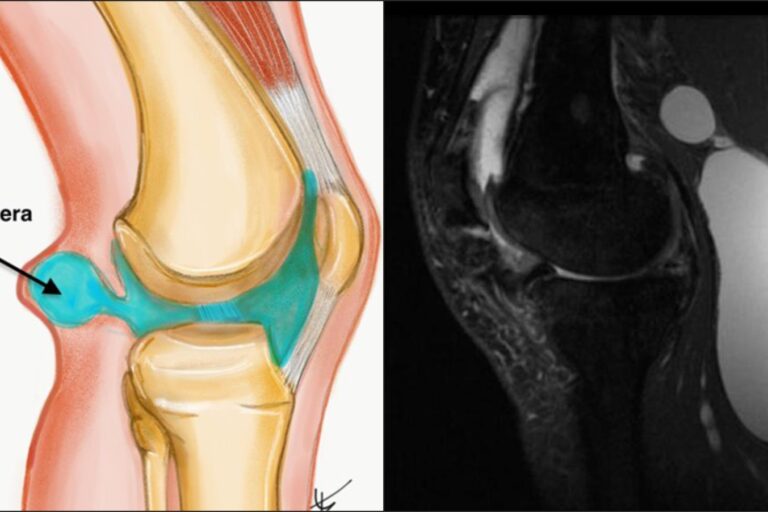

Jako ortopeda często spotykam pacjentów, którzy zaczynają biegać i na samym początku mają dolegliwości bólowe. Bardzo często są to osoby w wieku ok. 30-40 lat, które dotychczas spędzały czas mało lub niezbyt aktywnie.  Po nagłym oderwaniu od biurka, ich układ kostno-mięśniowy nie jest przygotowany do obciążeń treningowych, co skutkuje uszkodzeniami mięśniowo-kostnymi a w konsekwencji kontuzjami. Jest to bardzo deprymujące i zniechęcające. Ja jednak uważam, że nie ma powodów do rezygnacji z biegania! Nikomu nie odbieram prawa zostać maratończykiem! Czeka nas jednak więcej pracy. Być może należy zrobić krok w tył i zacząć od ćwiczeń rozciągających i ogólnorozwojowych, które stopniowo należy łączyć z treningiem biegowym. Należy tylko przygotować organizm do obciążeń biegowych. Bardzo często nasze stawy nie są rozćwiczone, a mięśnie rozciągnięte, podczas biegu nie pracują prawidłowo i podlegają niefizjologicznym obciążeniom, co jest powodem kontuzji.

Dobrym przykładem takiej sytuacji jest mój były pacjent, a obecnie kolega i biegacz –  Robert Buczek, który borykał się z bólem obu kolan i czuł się wykluczony ze sportowego życia. W wieku lat 47 Robert przeszedł kilka zabiegów operacyjnych na oba kolana (razem 7). Po operacjach, Robert rozpoczął treningi w kwietniu 2014 roku i od tego czasu przebiegł 9 maratonów, uzyskując swój najlepszy wynik 3.35,59 i to nie jest jego ostatnie słowo! Przed pierwszym zabiegiem operacyjnym ważył około 85kg, a obecnie 72kg. Wcześniej nie uprawiał żadnego sportu, w wieku lat 50 został aktywnym sportowcem amatorem. Jego przykład potwierdza, że można osiągnąć sukces tylko trzeba chcieć, wierzyć w siebie i dobrze się przygotować do podjęcia wyzwania.